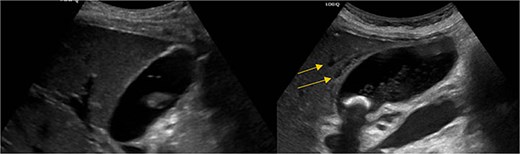

Stat CT scan showed new onset pericholecystic edema and hyperdense material within the common bile duct (CBD), not previously seen (Fig. 2). Stat Ultrasound confirmed findings of new onset acute cholecystitis (Fig. 3). Given the patient’s surgical history of gastric bypass, the decision was made to proceed with a robotic cholecystectomy with transcystic common bile duct exploration.

Hyperdense material (arrows) found in the CBD on the post-HIDA CT (right) that was not previously seen on the pre-HIDA CT on admission (left).

Pericholecystic fluid (arrows) and positive sonographic murphy sign present on the post-HIDA ultrasound (right) that was not previously seen on the pre-HIDA ultrasound on admission (left).

Our patient did not show radiographic evidence of choledocholithiasis prior to undergoing her HIDA scan. The HIDA scan itself was negative for cholecystitis and showed a normal EF (62%). The patient then had migration of debris into her CBD in the following 48 h. It is hypothesized that the HIDA scan was the inciting factor for the development of this patient’s ascending cholangitis.